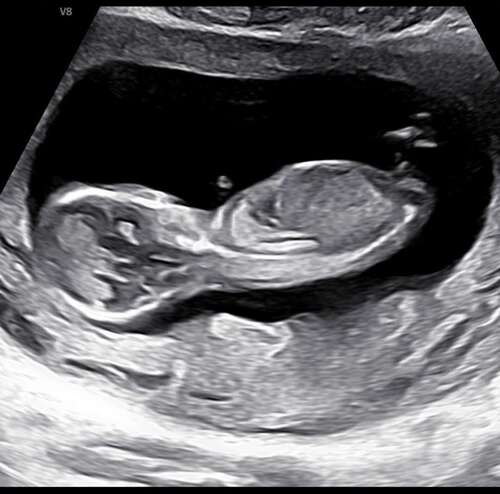

Kunnen jullie zien wat het wordt? Dit is de meest duidelijke foto die ik heb. 13+1 vandaag!

Kunnen jullie zien wat het wordt? Dit is de meest duidelijke foto die ik he ...

Durf het niet te zeggen. Ik zie ook een beentje ervoor dus lastig